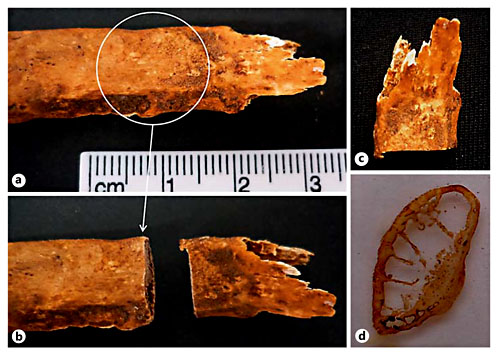

Of the 6 bone elements selected for histological analysis, 5 presented bone calluses with a consolidated and healed appearance (table 3). That is, the calluses appeared slightly elevated from the bone surface and presented a dense and smooth outer shell. Only the 4th right rib of the Sk. 1,138 individual showed an unconsolidated callus. Depending on the bone element, the callus morphology ranged from a sharp outlook to a mount-shaped or round relief (e.g. Sk. 119; fig. 1a-d). In 2 individuals (Sk. 54 and Sk. 198), the fracture had introduced slight structural changes in the bone architecture (fig. 2a-d, 3a-c). In the case of the Sk. 198 right fibula, an inefficient stabilization had caused a malalignment of the shaft with an overlap of the broken ends and subsequent bone shortening. In addition to some structural changes, a small cloaca (∼1 mm) with remodeled contours (anterior portion) and a patch of periosteal new bone formation (lateral portion) were observed in the Sk. 54 tibia bone callus. Healed fractures were seen in the ribs and at the distal extremity of the Sk. 1,196 radii, causing a slight epiphysis malalignment (fig. 4a-b2). In the unhealed rib fracture (Sk. 1,138), the broken edges presented an irregular, smooth, and polished morphology. Surrounding the affected area, deposits of periosteal new bone were seen detached from the surface. No ‘movable' joint-like structure was identified at the fractured ends (fig. 5a-d).

a Sternal end of the 9th right rib of an adult female (Sk. 119, 64 years old) who died of bronchopneumonia. b Detail of the area sampled for analysis showing a slight round elevation (white arrow). c Rib section collected for histological analysis. d Detail of the bone sample after slide preparation, in which is visible an accumulation of bone on the visceral surface.

a Sternal end of the 9th right rib of an adult female (Sk. 119, 64 years old) who died of bronchopneumonia. b Detail of the area sampled for analysis showing a slight round elevation (white arrow). c Rib section collected for histological analysis. d Detail of the bone sample after slide preparation, in which is visible an accumulation of bone on the visceral surface.